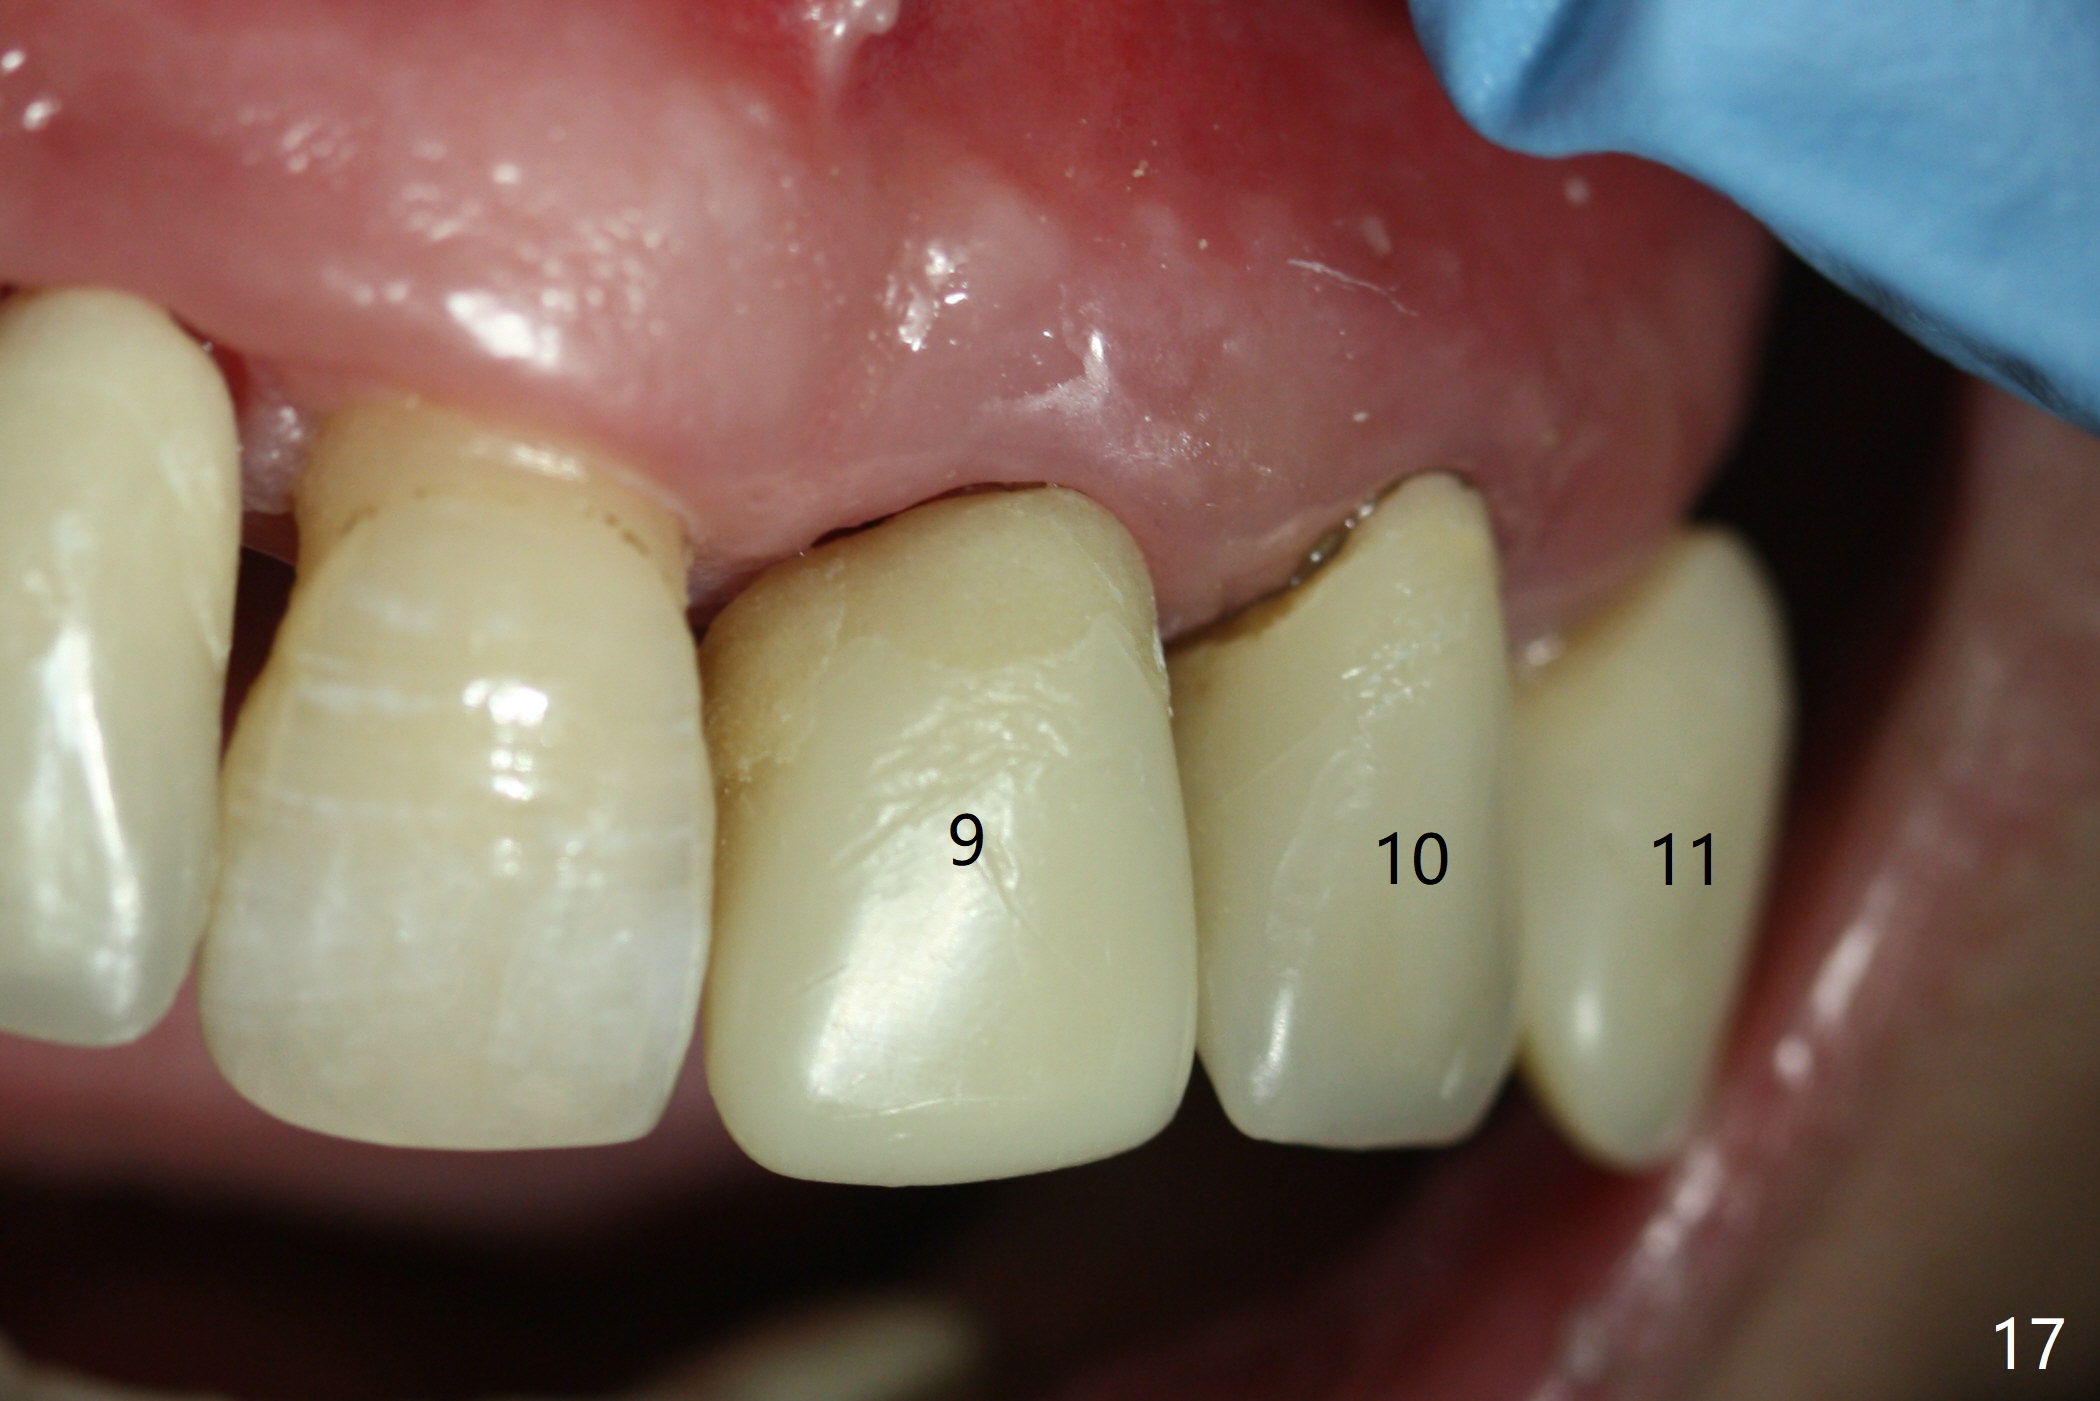

The patient returns 8 days postop, uncomfortable with overhang in the provisional (Fig.10 *). The sockets appear to be healing with loose bone graft (Fig.11) when the provisional is removed for trimming (Fig.12). Six (for #7,13) and seven (#9-11,15) months postop, the soft (Fig.13,17) and hard (Fig.14-16,18) tissues heal. It appears that the trajectory at #9,11 and 13 should be changed by using angled abutments (Fig.18,19 (panoramic X-ray taken 2 months earlier)) before provisional and final restoration.